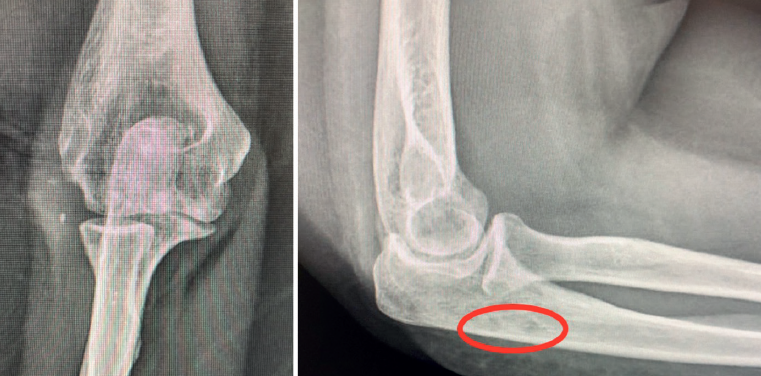

Following an immediate postoperative period (Figure 9) without complications and with adequate rehabilitation, the patient has been able to return to her normal life four and a half months after surgery. Upon exploration, the elbow proved stable, with a full joint motion range, and the patient was able to perform axial loading without pain or failure sensation (Figures 10A and 10B). The radiographs evidenced the reduced elbow (Figure 11).